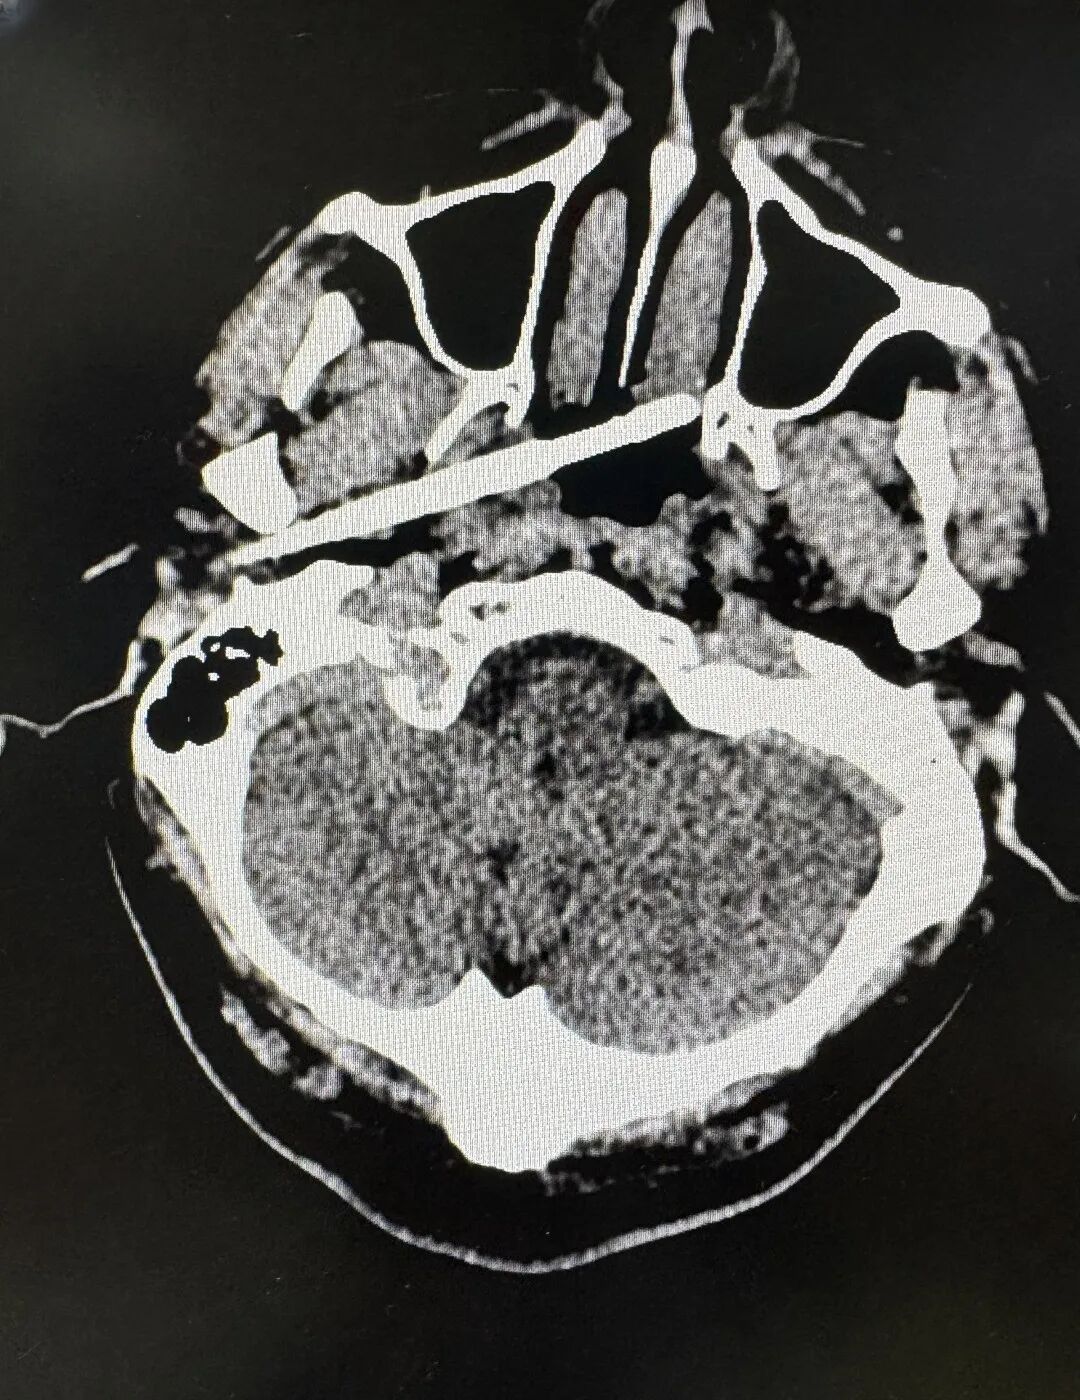

男子被一根筷子从外耳道上方插入

穿透侧颅底和咽旁的间隙

直抵鼻咽部

筷子尖端距离颈内动脉仅5毫米

近日,东莞45岁男子意外被一根筷子从耳部插入颅底,筷子被折断,断端残留在体内。更令人揪心的是,筷子不仅穿透了耳部骨质,筷子尖端距离颈内动脉仅5毫米。颈内动脉是大脑供血的主干线之一,一旦破裂,可导致瞬间大出血死亡。